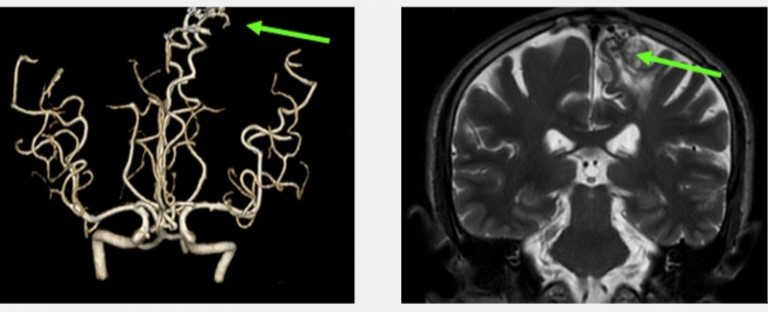

再者,比喻說我們人體就如一部汽車,政府規定汽車每一年都要例行檢查汽車的零件,看看是否安全行駛,不會在駕駛中失去安全操作而發生意外。然而,抽血檢查就像放取汽車偈油來檢查一樣,不能反影汽車內部零件的耗損和安全性。那麼要防止人體腦中風意外的發生, 就是不能單單透過抽血檢驗,而是要利用三維立體腦血管造影,作出詳盡的人體零部件篩查。如果例行的身體檢查包括了三維立體腦血管造影,腦神經外科醫生就可以在患者沒有症狀之前,找出先天性或後天性的計時炸彈,在其未爆發前將其拆除,來避免中風。

先天性的大腦動靜脈畸形血管瘤(Congenital Cerebral Arteriovenous Malformation)

一般人亦以為中風和年齡一定有關係,然而這是錯誤的,任何年齡即使是小孩也有機會中風。皆因中風是腦血管疾病所致,而我們每人無論任何年紀也有機會患上先天、或後天的腦血管疾病。小孩和少年的中風,可以是患有先天性的大腦動靜脈畸形血管 (Congenital Cerebral Arteriovenous Malformation) 所導致的出血性中風。

兩位分別是16歲的少年和56歲的男士,在沒有任何徵象之下做了詳盡的身體檢查,三維立體腦血管造影顯示兩人的大腦都有先天性的腦血管動靜脈畸形,在專科醫生建議之下透過了一段時間的觀察和保守治療,其後利用了微創內血管治療加上放射治療,畸形血管得到了有效的根治,病人與生俱來的大腦炸彈得到了拆除,減低了他們將來出血性中風的可能性。